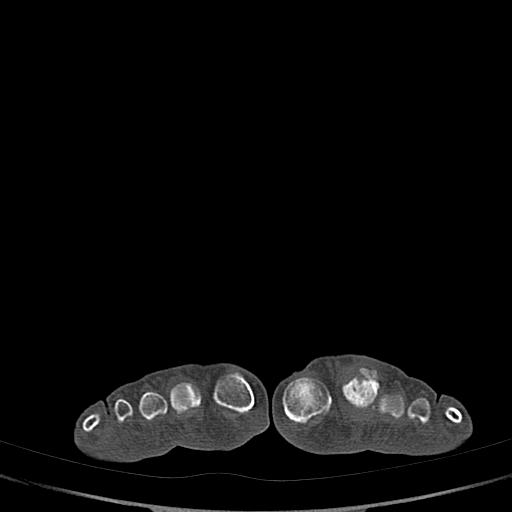

男72岁左侧跖趾关节肿痛15年,查压痛。

我也见过一位病人但是她才19岁,后来考虑还是慢性炎症

考虑退行性骨关节病。